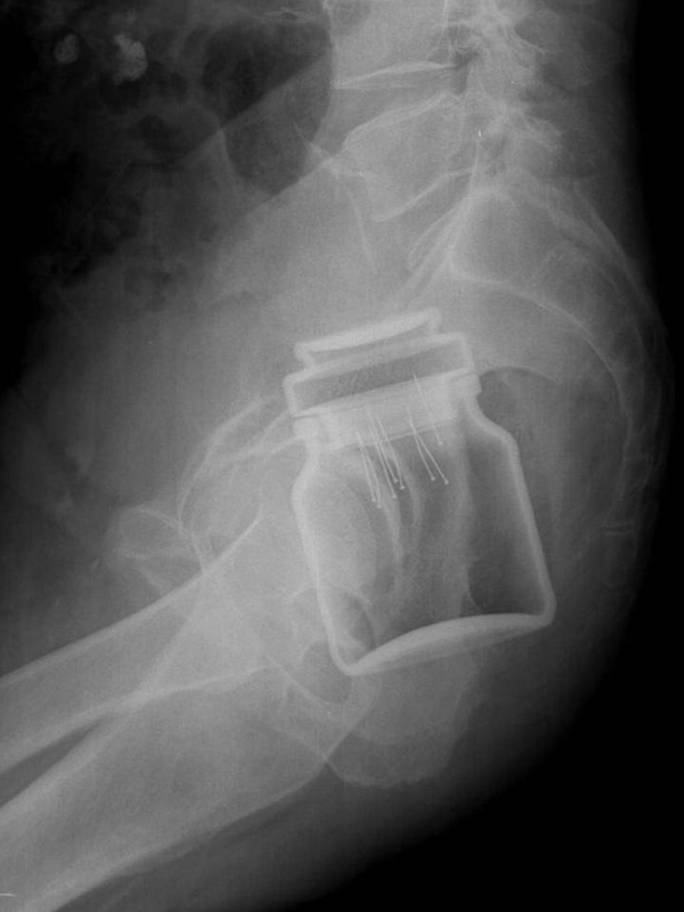

Ihmiset ovat todella outoja olentoja ja meille voi tapahtua uskomattoman outoja asioita. Nämä röntgenkuvat järkyttävät jopa ne, jotka luulevat nähneensä kaiken.

Radiologi so tako že precej navajeni, da na rentgenskih posnetkih vidijo čudne stvari in nekatere izmed teh, ki smo jih za vas zbrali v galeriji, jih sploh niso presenetile. Tukaj je 15+ odštekanih in na trenutke šokantnih rentgenskih posnetkov.